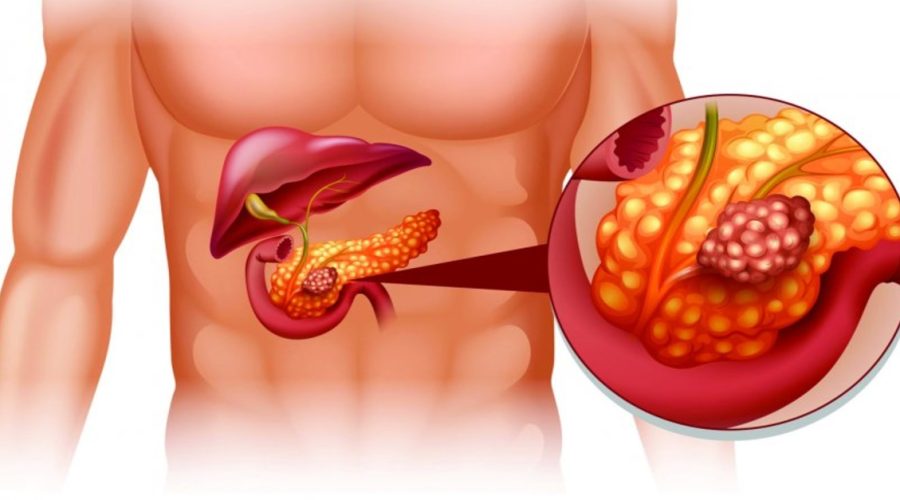

Continue lendoFique atento aos sinais e sintomas comuns de Câncer de fígado

O câncer de fígado é uma condição grave que afeta milhões de pessoas em todo o mundo. Conhecer os sinais e sintomas comuns dessa doença […]